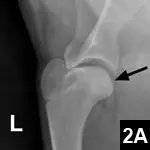

Shoulder Radiographs: Lateral views of both the left and right (Figures above) shoulders were performed. Craniocaudal views were also obtained (not shown).

Figures above. Lateral views of the left and right shoulders.

Radiographic Findings: Subtle subchondral lucencies were identified along the caudal margin of both humeral heads, supporting osteochondrosis (OCD). No panosteitis or other abnormalities are detected.

Figures 2A and 2B. Same images as Figures 1A and 1B, but with arrows pointing to the subchondral defects._